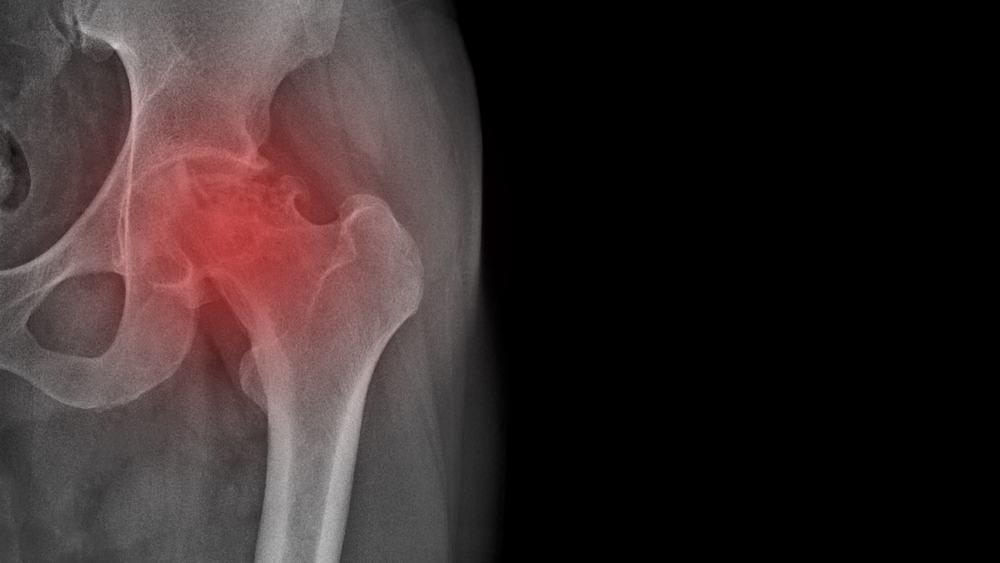

- Hoại tử chỏm xương đùi: là bệnh có tổn thương hoại tử tế bào xương và tủy xương do bị thiếu máu nuôi dưỡng phần trên chỏm xương đùi. Vùng hoại tử lúc đầu tạo ra các vùng thưa xương, các ổ khuyết xương, về sau dẫn đến gãy xương dưới sụn, cuối cùng gây xẹp chỏm xương đùi, thoái hóa thứ phát và mất chức năng của khớp háng, dẫn đến tàn phế